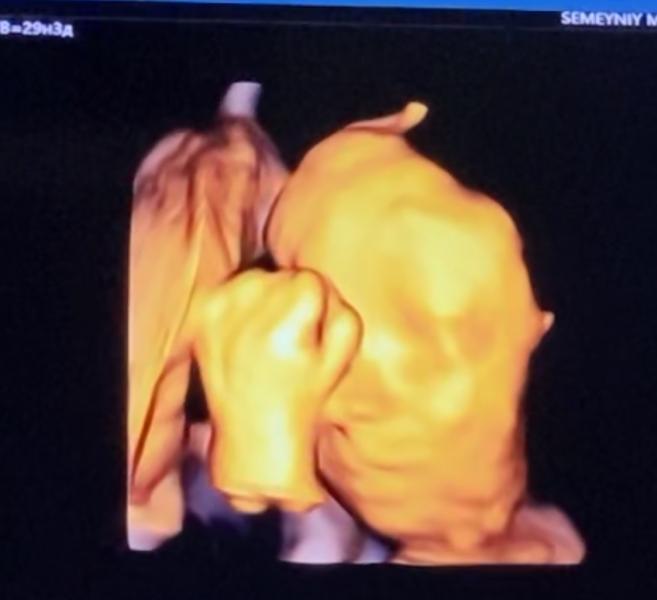

Привет 👋 #декрет #30недель 😁 Наконец-то мы добрались до УЗИ и увидели малышку 😍она такая забавная, все время улыбалась, потом закрылась ручкой и отвернулась 😁типа хватит 👌😉 Врач узи сказала- какая симпатичная малышка 🤗😍😉👌выходим на финишную прямую🙏🏼